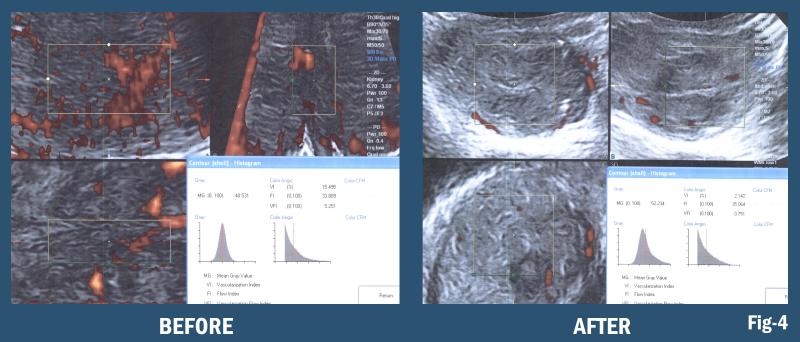

Quantifiable Digital Scanning and Image Guided Interventions

4-D imaging is real-time observation of a 3-D data set that permits image guided biopsy of the most virulent area of the infiltrate or tumor, targets the densest area of B-lines or neovascularity and allows the pathologist to focus on the most suspicious region of the lymph node mass excised during surgery. Similarly, during real time exam the fluid content of a pleural complex cyst maybe aspirated under better visual control and perilesional vessels avoided in a timely manner. This feature enhances the reliability of image guided treatments and fusion of this data set with computed tomography (CT) or magnetic resonance imaging (MRI) scans.

3-D/4-D Doppler Histogram